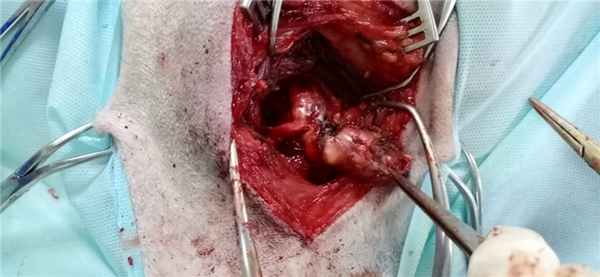

В 2005 г., спустя 17 лет с момента начала заболевания, стало вновь снижаться зрение на левый глаз, и пациентка впервые обратилась в НИИ нейрохирургии им. Н.Н. Бурденко. При обследовании выявлены зрительные расстройства: острота зрения слева — светоощущение; грубый парез третьего нерва слева (птоз, глазодвигательные нарушения). При КТ — опухоль левой орбиты. Произведено удаление опухоли, которая располагалась в верхушке орбиты и распространялась на верхнюю глазничную щель и зрительный канал. Гистологический диагноз (04.08.05): нейрофиброма. После операции: репозиция глазного яблока при сохраняющемся птозе верхнего века и частичном регрессе глазодвигательных расстройств. В августе 2008 г. вновь госпитализирована в НИИ нейрохирургии в связи с прогрессированием заболевания, развитием клиники объемного поражения левой орбиты в виде экзофтальма 5 мм и нарастания зрительных расстройств до амавроза. Рентгенологически определялась опухоль в области верхушки левой орбиты. Произведено удаление опухоли. На операции в области верхушки глазницы под надкостницей определялась светло-желтого цвета, плотной консистенции опухоль. Опухоль не инфильтрировала окружающие структуры и была удалена узлом. При контрольной КТ с контрастным усилением остатков опухоли не выявлено. Гистологический диагноз: нейрофиброма, индекс лечения Ki-67 составил 5% (см. рисунок, I). Рисунок 1. Нейрофиброма 2008 г. ( I), MPNST — 2010 г. (II) и 2012 г. (III). а — КТ; б, в — гистологические препараты; окраска гематоксилином и эозином; в — Ki-67: 50% (I), 10% (II), 30% (III). После операции экзофтальм регрессировал, наросли глазодвигательные нарушения.

Очередной рецидив заболевания отмечен в начале 2010 г. Ухудшение клинически проявлялось экзофтальмом, отеком век, гиперемией конъюнктивы. При КТ с контрастным усилением верифицирован рецидив опухоли медиальных отделов глазницы. В апреле 2010 г. в НИИ нейрохирургии произведено удаление опухоли, которая была плотной, кровоточивой, бугристой, серого цвета, заполняла и растягивала мышечную воронку глазницы, смещала глазное яблоко кпереди и медиально. Опухоль была связана с прилежащими мышцами, орбитальной клетчаткой. Опухоль отделена от глазного яблока, прилежащих отделов зрительного нерва и удалена в пределах видимости полностью.

Гистологическое заключение: нейрофиброма со злокачественной трансформацией в злокачественную опухоль оболочек периферического нерва (MPNST). Индекс лечения Ki-67 равен 10% (см. рисунок, II). При контрольной КТ остатков опухоли не выявлено. Клинически после операции отмечался регресс экзофтальма; сохранялись офтальмоплегия, амавроз, птоз верхнего века. По месту жительства в июле 2010 г. проведена лучевая терапия в СОД 63 Гр. С осени 2012 г. вновь стал нарастать экзофтальм слева, появились боли в левой глазнице. При контрольной КТ (ноябрь 2011 г.) выявлен рецидив опухоли в левой глазнице. Помимо этого развился левосторонний кератоувеит с угрозой перфорации глазного яблока. При УЗИ выявлено образование в орбите, вплотную подходящее к заднему полюсу глаза. Учитывая наличие амавроза, офтальмоплегии, трофических расстройств, а также высокий риск перфорации глазного яблока, было принято решение об удалении опухоли вместе с глазным яблоком, операция выполнена в НИИ нейрохирургии 14.02.12 г. При контрольной КТ остатков опухоли не выявлено.

Гистологическое заключение — злокачественная опухоль оболочек периферического нерва (MPNST). Индекс лечения Ki-67 равен 30% (см. рисунок, III). Проведена лучевая терапия в СОД 66 Гр. На момент написания статьи клинико-рентгенологических признаков рецидива нет.

Пациентка К., 65 лет. Из анамнеза известно, что в 1988 г. отметила снижение зрения слева, двоение предметов перед глазами. Обследована в МНИИ ГБ им. Гельмгольца, выявлено снижение остроты зрения на левый глаз до 0,7; при КТ выявлена опухоль левой орбиты, произведено оперативное вмешательство - удаление опухоли. Гистологический диагноз (сентябрь 1988 г.): «нехромафинная параганглиома». После операции зрение восстановилось, глазодвигательные расстройства регрессировали полностью. Около 5 лет больная наблюдалась в МНИИ ГБ им. Гельмгольца, состояние оставалось стабильным, рентгенологически признаков рецидива не определялось. В 1990 г. пациентке проведено комбинированное лечение (хирургическое удаление опухоли с последующей радиотерапией) опухоли кожи (базалиомы) в области fossa canina слева. В 2005 г., спустя 17 лет с момента начала заболевания, стало вновь снижаться зрение на левый глаз, и пациентка впервые обратилась в НИИ нейрохирургии им. Н.Н. Бурденко. При обследовании выявлены зрительные расстройства: OS – светоощущение; грубый парез III нерва слева (птоз, глазодвигательные нарушения). При КТ – рецидив опухоли левой орбиты. Произведено повторное удаление опухоли, которая располагалась в верхушке орбиты и распространялась на верхнюю глазничную щель и зрительный канал. Гистологический диагноз (04.08.2005): нейрофиброма. После операции: репозиция глазного яблока при сохраняющемся птозе и частичном регрессе глазодвигательных расстройств. В августе 2008 г. вновь госпитализирована в ИНХ в связи с прогрессированием заболевания, развитием клиники объемного поражения левой орбиты в виде экзофтальма 5 мм и нарастания зрительных расстройств до амавроза. Рентгенологически определялась опухоль в области верхушки левой орбиты. Произведено удаление опухоли. На операции в области верхушки глазницы под надкостницей определялась светло-желтого цвета, плотной консистенции опухоль. Опухоль не инфильтрировала окружающие структуры и была удалена узлом. При контрольной КТ с контрастным усилением остатков опухоли не выялено. Гистологический диагноз: нейрофиброма. Ki-67 – 5% (Рис. 1). После операции экзофтальм регрессировал, наросли глазодвигательные нарушения.

Очередной рецидив заболевания отмечен в начале 2010 г. Ухудшение клинически проявлялось экзофтальмом, отеком век, гиперемией конъюнктивы. При КТ с контрастным усилением верифицирован рецидив опухоли медиальных отделов глазницы. В апреле 2010 г. госпитализирована в ИНХ для хирургического лечения. Произведено удаление опухоли: разрез мягких тканей по старому рубцу. Отслоена рубцово-изменённая височная мышца. Скелетированы края послеоперационного дефекта латеральной стенки глазницы. Ткани глазницы уплотнены, рубцово- изменены. Подход к мышечной воронке глазницы путем рассечения рубцовой ткани между латеральной и верхней прямыми мышцами. Выявлена плотная, кровоточивая, бугристая опухоль серого цвета, заполняющая и растягивающая мышечную воронку глазницы, смещающая глазное яблоко кпереди и медиально. Опухоль связана с прилежащими мышцами, орбитальной клетчаткой. Произведено отделение опухоли от глазного яблока и прилежащих отделов зрительного нерва. Кзади опухоль распространялась в верхнюю глазничную щель и зрительный канал. Произведен гемостаз. В ложе оставлен ирригатор, выведенный через контрапертуру на коже головы. Швы на мягкие ткани.

Гистологическое заключение: нейрофиброма со злокачественной трансформацией в злокачественную опухоль оболочек периферических нервов (MPNST). Ki-67 10% (Рис. 2). При контрольной КТ данных за остатки опухоли выявлено не было. Клинически после операции отмечался регресс экзофтальма; сохранились офтальмоплегия, амавроз, птоз. По месту жительства в июле 2010 г. проведена радиотерапия в СОД 63 Гр. С осени 2012 г. вновь стал нарастать экзофтальм слева, появились боли в левой глазнице. При контрольной КТ головного мозга (ноябрь 2011г) определяется рецидив опухоли в левой глазнице. Помимо этого развился левосторонний кератоувеит с угрозой перфорации глазного яблока. При УЗИ выявлено образование в орбите, вплотную подходящее к заднему полюсу глаза. В феврале 2012 г. госпитализирована в ИНХ для хирургического лечения. Учитывает наличие амавроза, офтальмоплегии, трофических расстройств, а также высокий риск перфорации глазного яблока, было принято решение об удалении опухоли вместе с глазным яблоком. 14.02.2012 г. произведена операция. При контрольной КТ головного мозга и глазницы данных за остатки опухоли не выявлено.

Гистологическое заключение - злокачественная опухоль периферических нервов (MPNST). Ki-67 – 30% (Рис. 3). Проведена ЛТ в СОД 66 Гр. На момент написания статьи клинико-рентгенологических признаков рецидива нет.